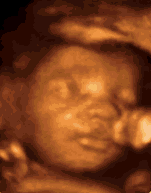

Kompleksowa opieka w ciąży: badania obowiązkowe, dodatkowe, ultrasonografia genetyczna - ocena przezierności karkowej, kości nosowej, test podwójny, potrójny, choroby wirusowe i pasożytnicze, prowadzenie ciąży, porodu, opieka poporodowa, ultrasonografia dopplerowska i 3D, 4D z możliwością nagrania na nośniki pamięci (badanie osobne niezwiązane z wizytą położniczą)